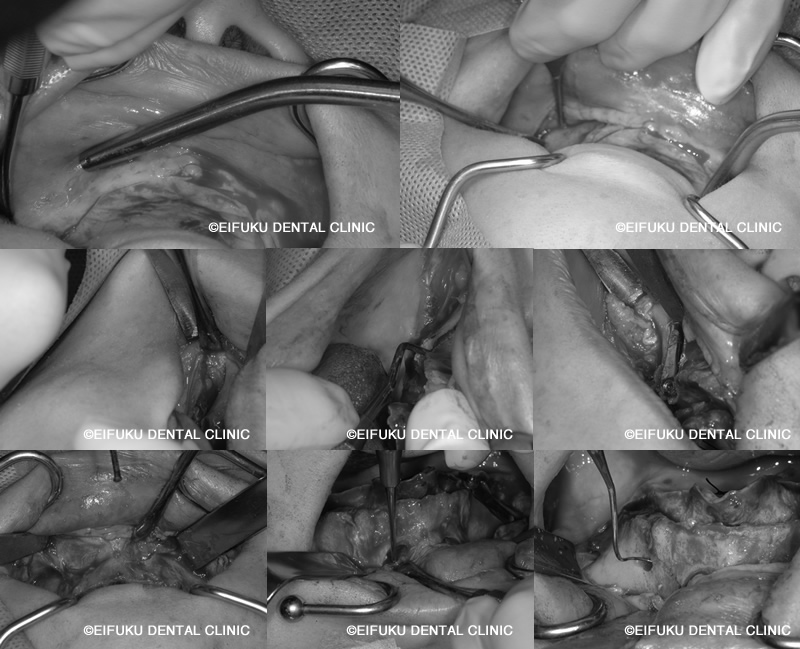

| コメント | 40代の男性、患者さんは、「歯が動いてしっかり噛めない」「歯ぐきから血が出る」「歯が割れてしまった」というお悩みで来院されました。 重度の歯周病と歯の破折が進行しており、上顎の多くの歯は保存が難しく、このままでは仕事や日常生活に支障が出るほど噛む力が低下している状態でした。「とにかく早く噛めるようになりたい」「総入れ歯にはしたくない」という患者さんのご希望から、上顎は左右の頬骨にインプラントを固定するザイゴマインプラントを用いたオールオン形式の治療計画を立案しました。 通常のオールオン4では骨量が不足しているケースでも、頬骨を利用することで強固な固定が得られ、ブリッジ状の固定式の歯を支えることが可能になります。精密検査のうえ、残存歯を抜歯しながら同時にザイゴマインプラントを埋入し、十分な初期固定を確認したうえで、その日のうちに固定式の仮歯を装着しました。術後まもなく柔らかい食事から再開でき、「ぐらぐらせずしっかり噛める」「人前で思い切り笑えるようになった」と大変喜んでいただけました。ザイゴマインプラントを用いたオールオン形式は、歯がボロボロで動いている、歯ぐきから血が出る、歯が割れて噛めないなど重度の症状でも、短期間でしっかり噛める状態を目指せる治療オプションです。 当院では、骨量不足や重度歯周病でお悩みの方に対しても、専門的なインプラント治療と丁寧なカウンセリングで、早期に「噛める」「見た目も回復する」ことを重視した治療をご提案しています。 |